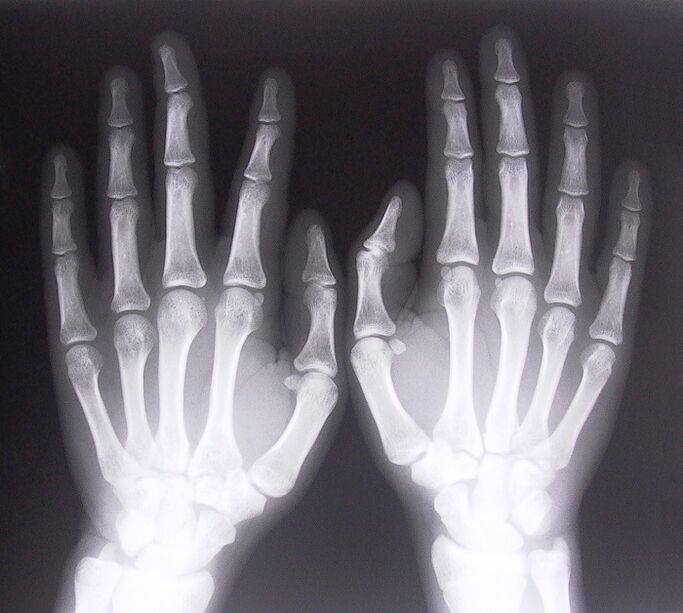

- Stenosing ligamentitis.To determine the cause of the disease, an x-ray is required.The symptoms are typical: painful movement of the hand, looping of the clenched palm.In addition, clicking noises can usually be heard when extending.

To begin treating joint pain in the fingers, you need to correctly determine what disease caused it.To determine what kind of disease a person has who feels pain in the joints when bending his arms, doctors recommend the following procedures:

- Take x-rays.